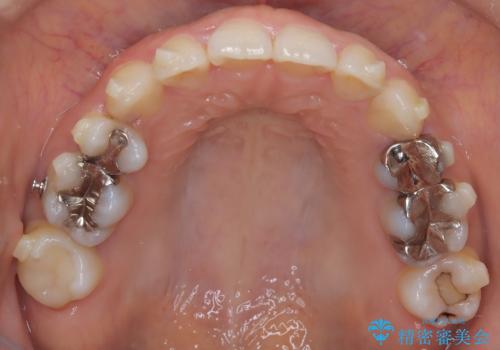

- 上下の歯の中心(正中)のズレと、口元の見た目を気にされて来院されました。精密な検査の結果、咬み合わせのバランスを整えながら、正中線を一致させる治療が必要と判断。患者様のご希望に合わせ、透明で目立ちにくいインビザライン(マウスピース矯正)による治療計画を立案しました。歯列全体を奥(遠心)へ移動させるためにゴムかけを併用。さらに、見た目を改善するため、既存の金属の被せ物をセラミッククラウンに交換することも治療計画に組み込みました。

今回の矯正治療では、透明なマウスピース型の装置インビザラインを使用しました。歯列を奥へ動かす遠心移動の効率を高めるため、患者様ご自身にゴムかけも行っていただきました。この併用によって、歯をより正確かつスムーズに動かすことができ、上下の歯の中心である正中線を一致させることが可能になりました。また、治療の最終段階では、以前から入っていた金属の被せ物を、天然歯に近い色合いのセラミッククラウンに交換。矯正治療と審美治療を組み合わせることで、機能的な咬み合わせの改善に加え、金属が見えない、より自然で美しい口元を獲得していただけました。